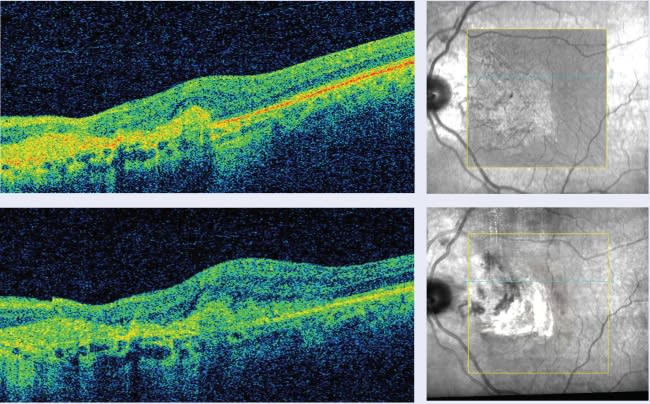

Images from the Cirrus HD-OCT demonstrate AMD progression over a 2-month period "If I diagnose a patient with dry AMD, I have him return based on the severity of AMD at either 6 months or a year, so that I can watch for signs of possible progression, which would trigger a referral to a specialist. But what about the gaps between visits? A patient may develop wet AMD but not recognize he is losing vision for up to 6 months. By the time he comes in for an appointment, he may already have some permanent damage. Having the technology to detect wet AMD earlier can help us save vision." |